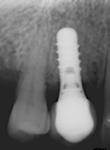

Der ses anterior trangstilling i begge kæber og overerupterede 1+1 og 2,1-1,2, hvilket resulterer i dybt bid med 2- tæt på ganepåbidning. Der er normale sidetandsrelationer, men der ses 5 mm horisontalt overbid (HOB) og 7 mm vertikalt

overbid (VOB). Papillen mellem 1+1 er betydeligt reduceret pga. fæstetab, og de mesialt kippede 1+1 har resulteret i en ”dark triangle”. Den facioorale funktion er for nuværende i.a. Panoramarøntgen (Fig. 1, I) viser marginalt knogletab i begge kæber og fravær af 8,7+7,8 og 8,7-8.